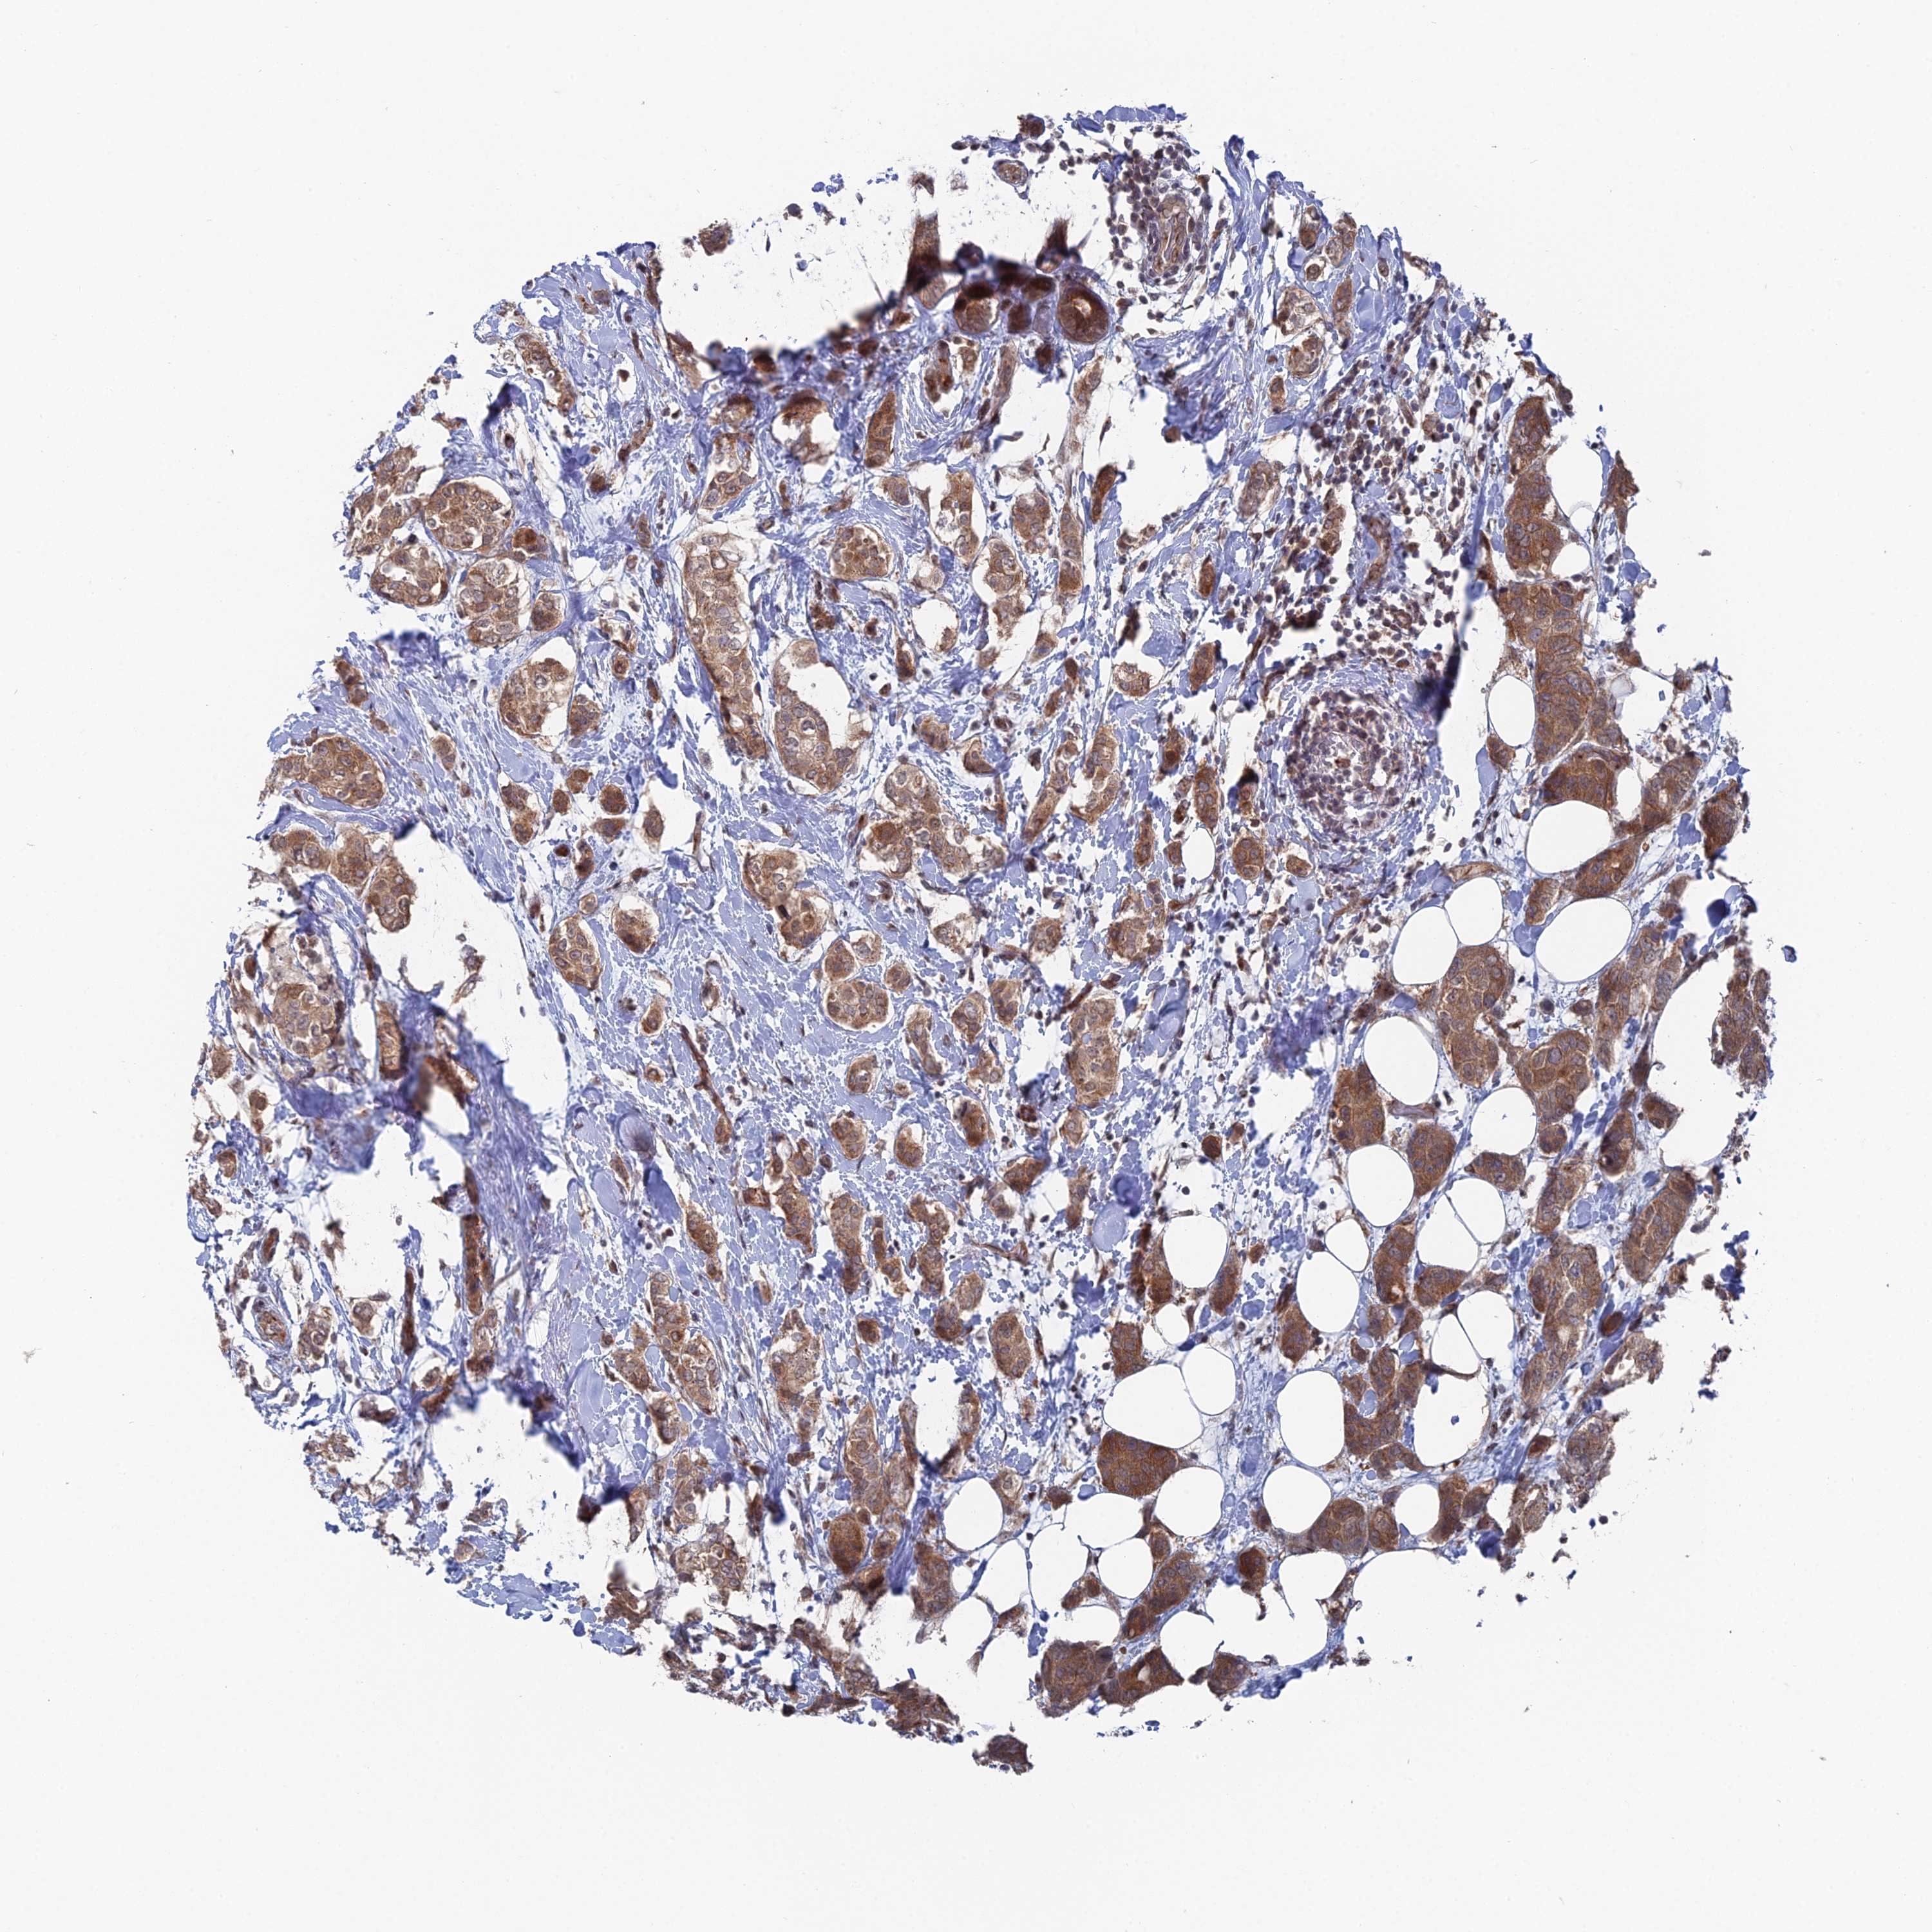

CANCER BREAST CANCER Show tissue menu

BRCA TCGA BRCA VALIDATION PROTEIN EXPRESSION